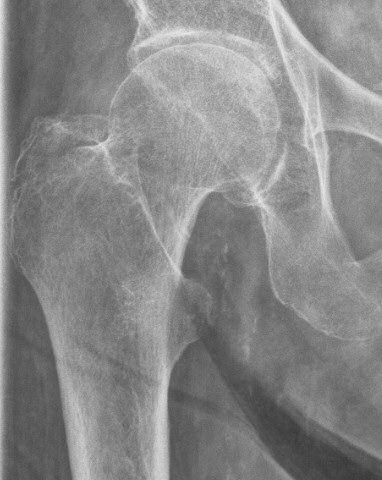

Trokanter majorfraktur, behandlades med direkt mobilisering

Skada: Fraktur trokanter major